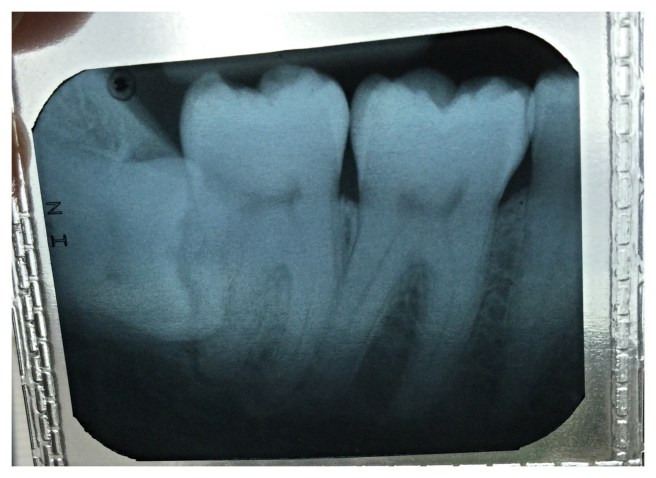

This has been a week of dental appointments. I am currently on two different antibiotics for a severe toothache that started last Wednesday. Apparently I have an infection under a wisdom tooth that never poked through. The offending bacteria somehow managed to wiggle its way out of reach of my brush and floss, and now it looks like the tooth will have to be extracted. My wisdom teeth have never caused me grief before so I’m a bit surprised that I have to deal with this at age 37. It would have been a much easier procedure in my teens…before those roots were fully formed. Not to mention this tooth is completely perpendicular to my molars back there. Look at that sucker! (It’s on the far left, under the gum, lying on its side.)